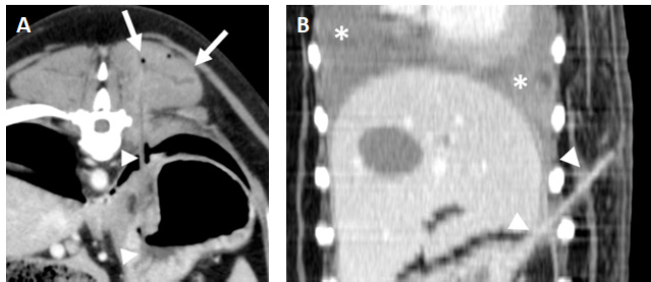

Fig. 2. A and B. Transverse and dorsal, post-contrast CT images (level −500 HU, width 1,400 HU) of the same patient showing a hyperattenuating (112 HU), 63 mm length × 1.3 mm width foreign body (arrowheads) lodged in the right caudal lung lobe and causing a small cavitary lesion (arrow). There is an asymmetric pleural effusion, more severe on the right side (asterisks). The right pulmonary lobes are decreased in volume with an almost generalized consolidation pattern, most likely secondary to atelectasis. C. Parasagittal post-contrast CT image (level −500 HU, width 1,400 HU) of a perforating wooden skewer foreign body from the stomach (arrowheads), perforating the pleural space and right caudal lung lobe which shows a focal increased attenuation and thickening of the visceral pleura. There is a mild volume of pneumothorax (asterisks). Note that the air within the pulmonary cavitary lesions or in the pleural space aids in the identification of these foreign bodies.

When part of the wooden skewer was traversing the pulmonary parenchyma (Fig. 2), the surrounding lung had increased attenuation and the visceral pleura was thickened, features previously described in the perforation site secondary to grass-awn migration and most likely indicative of pneumonia and pleuritis (Baudin Tréhiou et al., 2020). Additional cavitary lesions showing gas-fluid levels with a thin and well-defined wall were present in two dogs. These were interpreted as pulmonary traumatic pseudocysts formed by the retraction of surrounding lung tissue following pulmonary laceration (Cho et al., 2015; Bertolini et al., 2020). Abscess formation could not be ruled out but was considered less likely as usually shows thicker and irregular walls (Lamb and Neiger, 2000). Secondary bilateral and asymmetric pneumothorax was present in all pulmonary perforations, and this asymmetry correlated with the side of the perforation in all cases.

Fig. 3. Examples of gastric foreign bodies from the stomach with the ending tip in the paravertebral or thoracic wall soft tissues. A. Transverse post-contrast CT image (level 40 HU, width 250 HU) of a dog with a wooden skewer (arrowheads) extending from the stomach and ending in the left epaxial muscles. Mild fluid accumulation and emphysema are seen surrounding the ending tip of the foreign body (arrows). B. Dorsal post-contrast CT image (level 40 HU, width 250 HU) of a dog with a wooden skewer (arrowheads) perforating the gastric wall with an oblique orientation ending in the subcutaneous tissue of the left thoracic wall. A moderate bilateral pleural effusion is seen associated with this foreign body (asterisks).